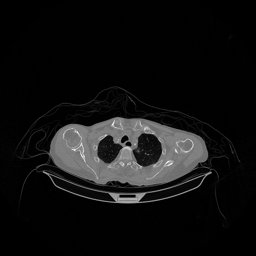

The experimental results on clinical head data are shown in Fig. 4. The reference images were reconstructed using the fast iterative shrinkage-thresholding algorithm (FISTA) with total variation regularization from non-truncated projection data. In the WCE reconstructions (Fig. 4(b)), severe truncation prevents accurate recovery of anatomical structures outside the FOV. Despite being trained solely on simulated data with a domain gap, all deep learning models can restore a substantial portion of the missing anatomy. Among them, the diffusion-based methods recover soft-tissue boundaries more faithfully than the conventional deep learning approach FBPConvNet, highlighting their stronger image generation capability. However, cDDPM reconstructions exhibit more noticeable noise than those from other methods, consistent with the simulated data results. The patchDiffusion model introduces artifacts within the FOV, likely due to its patch-wise processing strategy. While I2SB shares the same limitations as other diffusion models in perfectly restoring soft-tissue detail, it produces fewer residual noise patterns and fewer artifacts within the FOV boundaries. Overall, Fig. 4 demonstrates the strong efficacy of I2SB in reconstructing real CBCT data.